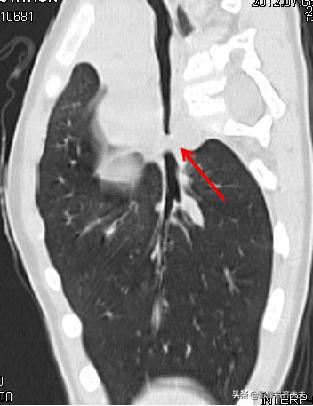

病例7、病史:患儿,女,16个月,吃饭呛咳,来院就诊。(图片来源:邯郸市第一医院)

图中CT轴位扫描及MPR冠状位重建,清晰显示左左侧支气管异物,红色箭头所示。

MinIP(最小密度投影重建)可准确直观显示异物的形态、大小、位置、堵塞程度等各种相关情况。可有效弥补X线胸片和常规CT诊断上的不足,作为支气管镜前筛查和手术定位的重要依据。